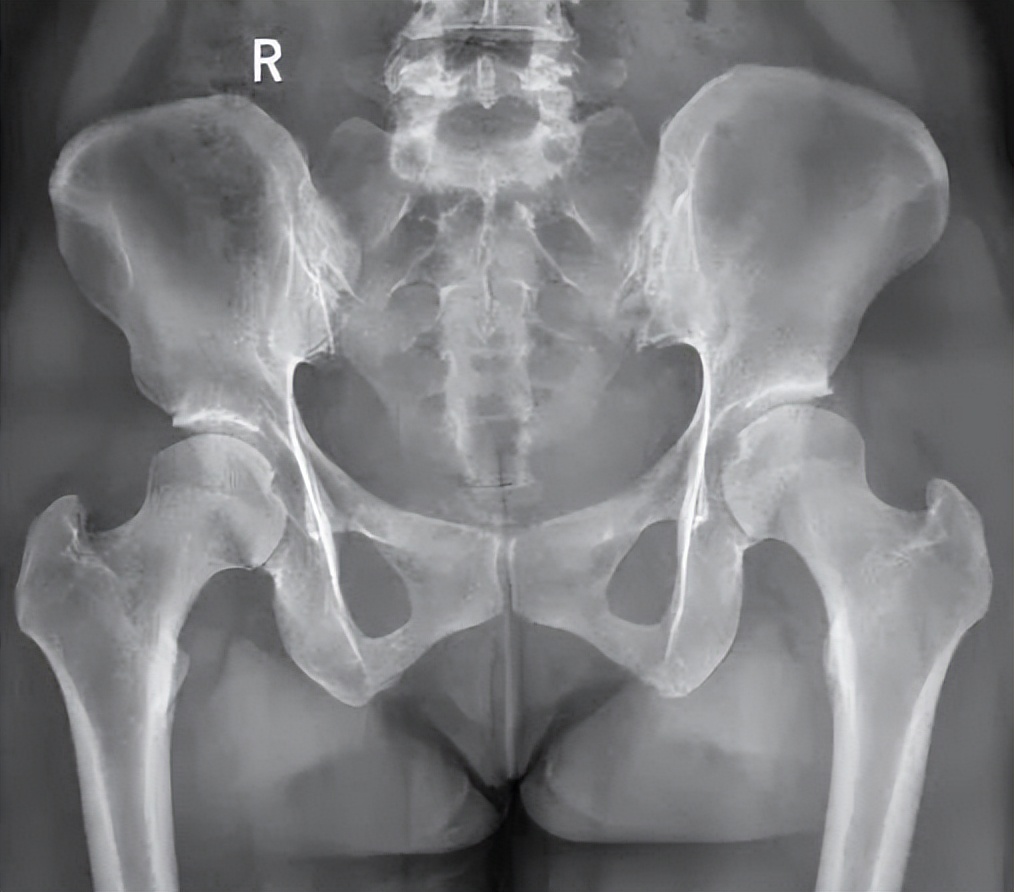

骨盆是躯干和腹部的底层,连接着下肢和脊柱,由髂骨、坐骨、耻骨构成。髂骨后部和中央骶骨连接形成骶髂关节。左右耻骨之间有纤维软骨连接,形成耻骨联合。

骨盆是由两侧的髋骨,正中间的骶骨,以及下面的尾骨组成的盆状结构,在骨盆的正上方是腰椎,骨盆不稳最大的影响是对我们腰椎的影响,如果骨盆长时间处于歪的状态的话,就会引起腰椎的侧弯,或者腰椎变得更直,进而影响到椎间盘,就可能导致椎间盘突出、慢性腰肌劳损、关节卡锁等相应问题。骨盆歪斜状态,会使左右两侧受力不均,造成骶髂关节损伤、盆底肌松弛无力、盆腔内血液循环障碍及慢性炎症等。

观察两侧髂嵴最高点,如果偏歪会出现一边高一边低现象;肩膀出现一边高一边低,大概率骨盆也会有问题;用双手去感受被测者髂前上棘位置,查看骨盆是否出现旋转;走路一脚重一脚轻,或者一只脚经常扭伤,都有可能存在骨盆旋转问题。对于专业的治疗师或医生来说,站立位评估以及仰卧位评估,直腿抬高试验或者影像学检查都可以很好的评估。